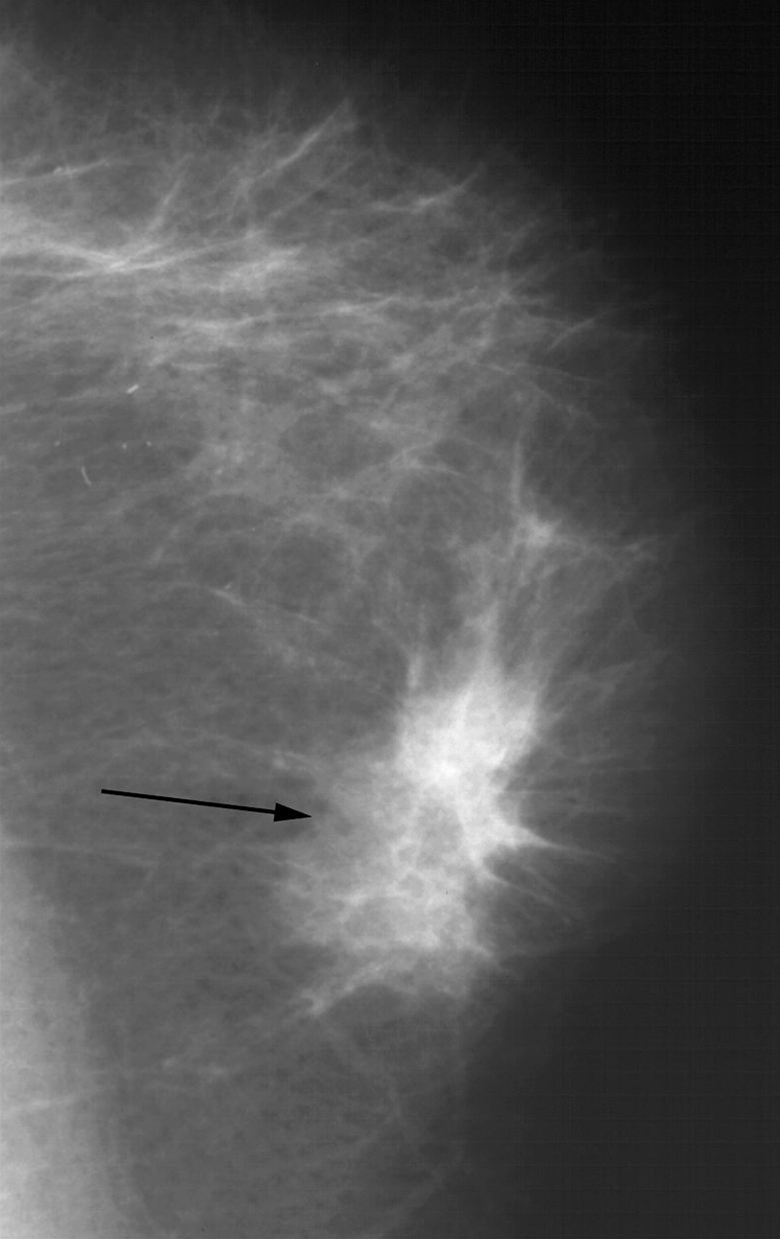

Skrå mammografi, som viser en fortætning (se pil) med stribeformede infiltrater i vævet. Typisk udseende ved brystkræft.